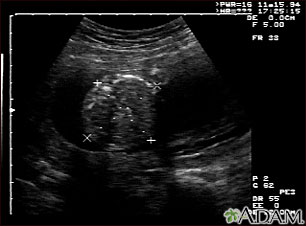

Ultrasound, normal fetus - abdomen measurements

This is a normal fetal ultrasound performed at 19 weeks gestation. Many health care providers like to have fetal measurements to verify the size of the fetus and to look for any abnormalities. This ultrasound is of an abdominal measurement. It shows a cross-section of the abdomen, and the measurements are indicated by the cross hairs and dotted lines.